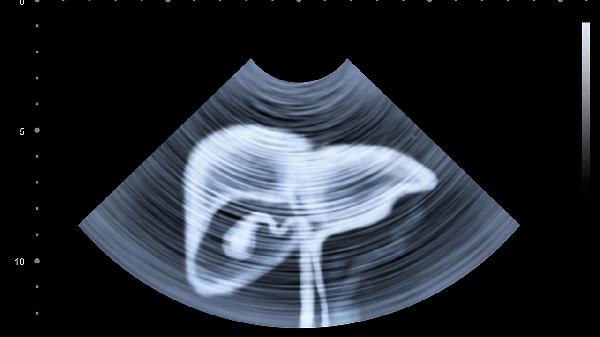

某些腹部疾病,如腹水、内脏下垂等,也可能导致腹部触感柔软。如果伴随腹痛、腹胀、体重下降等症状,应及时就医检查。医生可能会通过超声、CT等影像学检查明确病因,并根据具体情况采取药物治疗、手术治疗等方案。